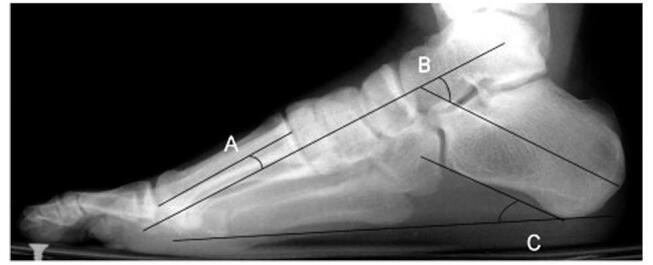

Our systematic review analyzed 26 studies with 8514 participants. Young age was a risk factor in four studies, and female gender in one. High body mass index, increased training hours, competitions, and intense preseason training also raised risk. Anatomical factors included lower calcaneal pitch angle, wider medial malleolar slip angle, higher Talocalcaneal angle, and lower limb varus malalignment. Stress fractures were higher among midfielders in one study, while two others found no positional differences. Additional risks were elevated parathyroid hormone, higher bone-specific alkaline phosphatase, lower 25OH levels, fasting, and perceived stress from negative life events.

我们的系统评价分析了26项研究,涉及8514名参与者。四项研究表明年龄小是一个风险因素,一项研究表明女性是风险因素。高体重指数、训练时间增加、比赛次数和季前强化训练也会增加风险。解剖学因素包括跟骨倾斜角较低、内踝滑动角较宽、距跟角较高以及下肢内翻畸形。一项研究表明中场球员应力性骨折发生率较高,而另外两项研究未发现位置差异。其他风险因素包括甲状旁腺激素升高、骨特异性碱性磷酸酶水平较高、25OH水平较低、禁食以及负面生活事件带来的感知压力。